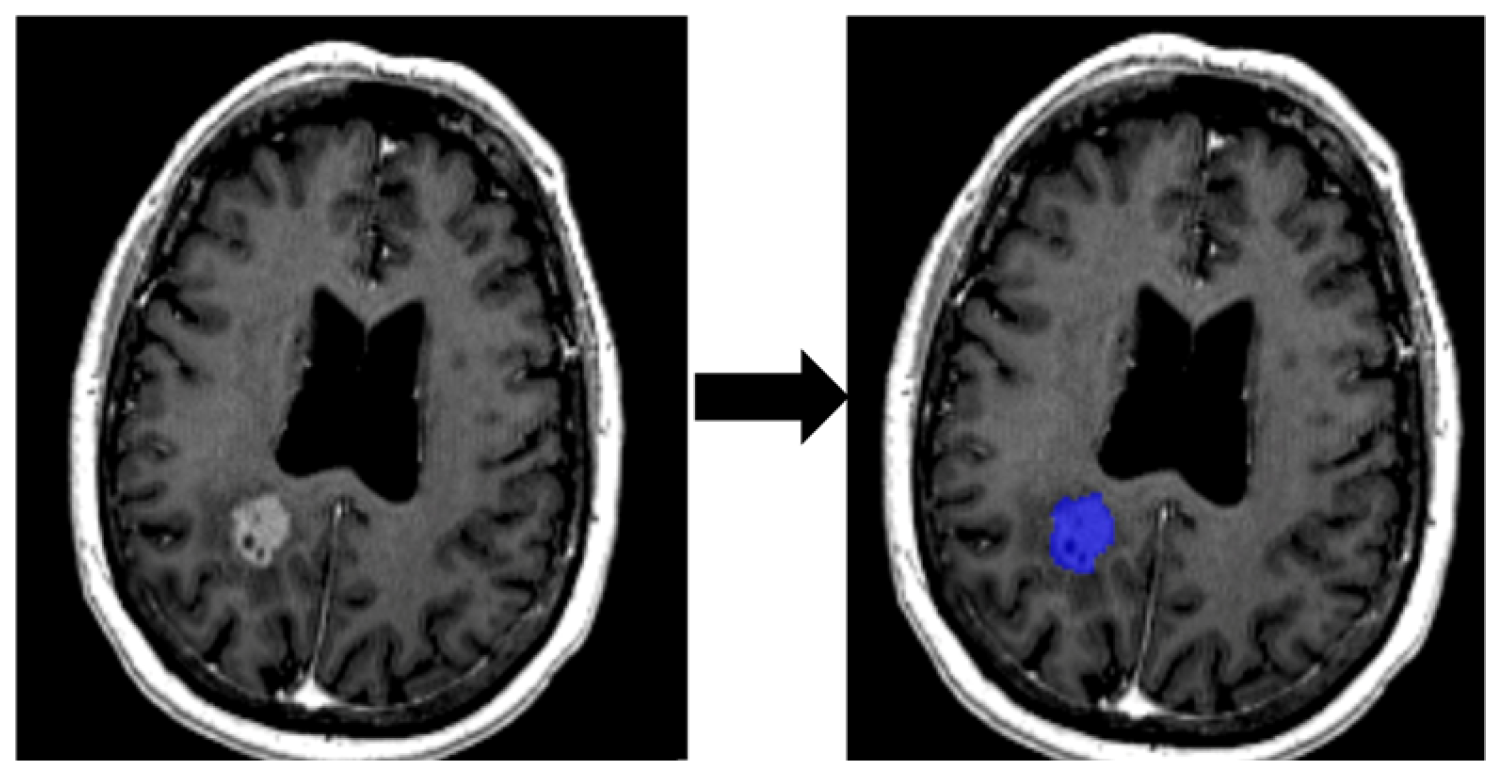

2.3.1. Segmentation of ROI